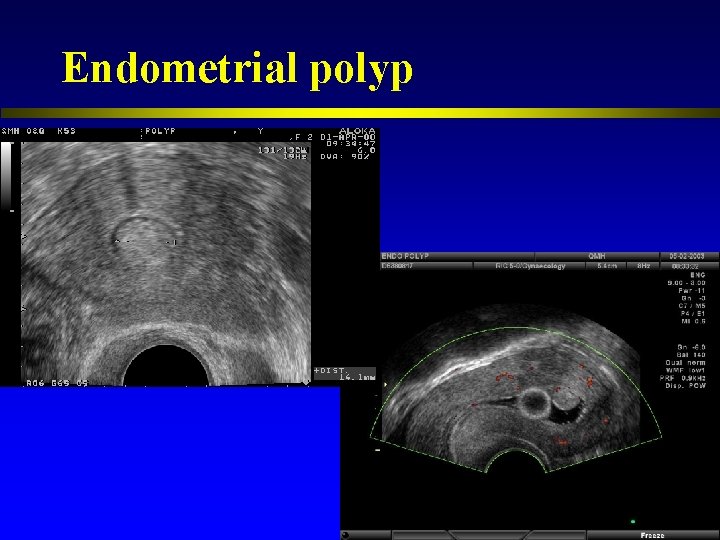

Endometrial polyp

Endometrial polyp